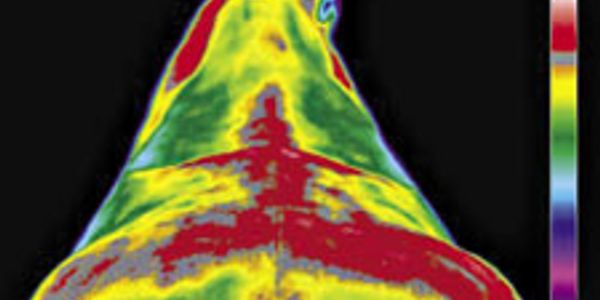

All heat patterns are based on normal physiology. After hundreds of examinations on horses’ backs using a thermal camera I will find the warmest area is almost always down the middle of the back. “When we start to see break-ups of these patterns, that’s a clue for us to look there more closely. “Sometimes hot spots are very important, but cold spots are just as important; a cold spot can be an area of swelling–where the circulation has decreased–and that area stays sore longer “We can do all sorts of things with IRT, and I find it invaluable in pinpointing all kinds of back problems and upper limb problems.Sometimes it can be difficult to detect. “Thermography can give us a look at the whole area. A Certified Thermographer along with Vet/ Farrier knows a certain image correlates with a certain problem. It can show us a sacroiliac [lower back] problem. I find thermography most useful for detecting something that’s causing a horse to be just slightly off. The horse isn’t lame, but the rider usually knows something isnt right and the veterinarian/ Farrier is left perplexed because they can’t see anything. There may be no obvious clinical signs, but a Thermal scan may identify something early as 2 weeks. This is a great diagnostic tool to be used in conjunction with other diagnostic tools x-rays,examinations etc.